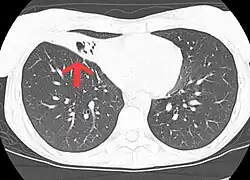

CT scan of patient with right middle lobe aspiration and Mycobacterium avium infection.

MAC usually affects patients with abnormal lungs or bronchi. However, Jerome Reich and Richard Johnson describe a series of six patients with MAC infection of the right middle lobe or lingula who did not have any predisposing lung disorders.[17][18]

The right middle lobe and lingula of the lungs are served by bronchi that are oriented downward when a person is in the upright position. As a result, these areas of the lung may be more dependent upon vigorous voluntary expectoration (cough) for clearance of bacteria and secretions.

Since the six patients in their retrospective case series were older females, Reich and Johnson proposed that patients without a vigorous cough may develop right middle lobe or left lingular infection with MAC. They proposed this syndrome be named Lady Windermere syndrome, after the character Lady Windermere in Oscar Wilde's play Lady Windermere's Fan. However, little research has confirmed this speculative cause.[19]